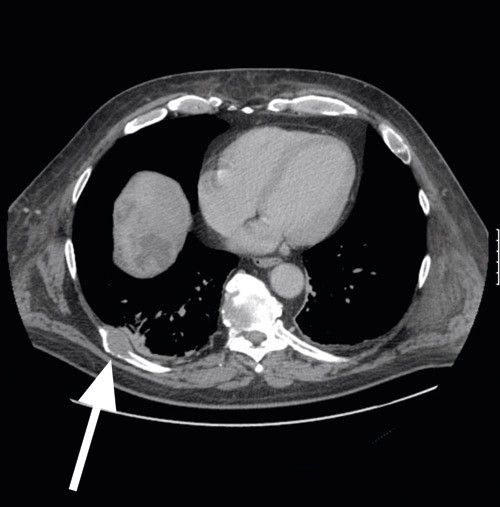

Pasienten ble så vurdert av øre-nese-hals-lege, som ikke fant tegn til malign sykdom i munnhule, hals eller svelg. Undersøkelse av perifert blod viste uttalt lymfopeni, men ellers normal mikroskopi og immunofenotyping. Undersøkelse av beinmarg viste kun uttalt lymfopeni, og ved immunofenotyping ble det ikke funnet patologiske forhold. CT-undersøkelse av abdomen viste imidlertid en stor tumor i høyre leverlapp (diameter 143 x 168 x 150 mm) og en liten tumor i venstre leverlapp (diameter 7 x 14 x 10 mm) (fig 2). CT-undersøkelse av thorax viste utstansede lesjoner i de tre første lumbalvirvlene forenlig med skjelettmetastaser. Baktil i høyre niende ribbein ble det påvist en destruerende tumoroppfylning som ekspanderte og infiltrerte åttende interkostalrom (fig 3). Alfaføtoprotein (AFP) var sterkt forhøyet (1 440 kU/l og steg senere til 1 600 kU/l)(normalt < 14).

Funnene av leversvulster sammen med metastaser til virvler og ribbein samt sterkt forhøyet alfa-1-føtoprotein var nærmest diagnostisk for hepatocellulært karsinom. Pasienten ble vurdert inoperabel både med hensyn til tumorreseksjon og levertransplantasjon.